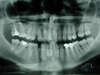

Les radios avant traitement